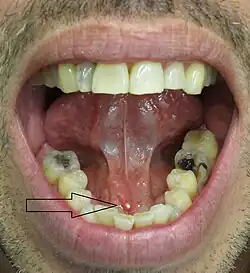

![]() Piedras de la glándulas salivales. | ||

El cálculo de la glándula salival (sialolito) es una concreción, principalmente de sales minerales de calcio (calculus) que se forma en los conductos de las glándulas salivales.[1]

La mayoría de este tipo de cálculo se forma en la glándula submaxilar.